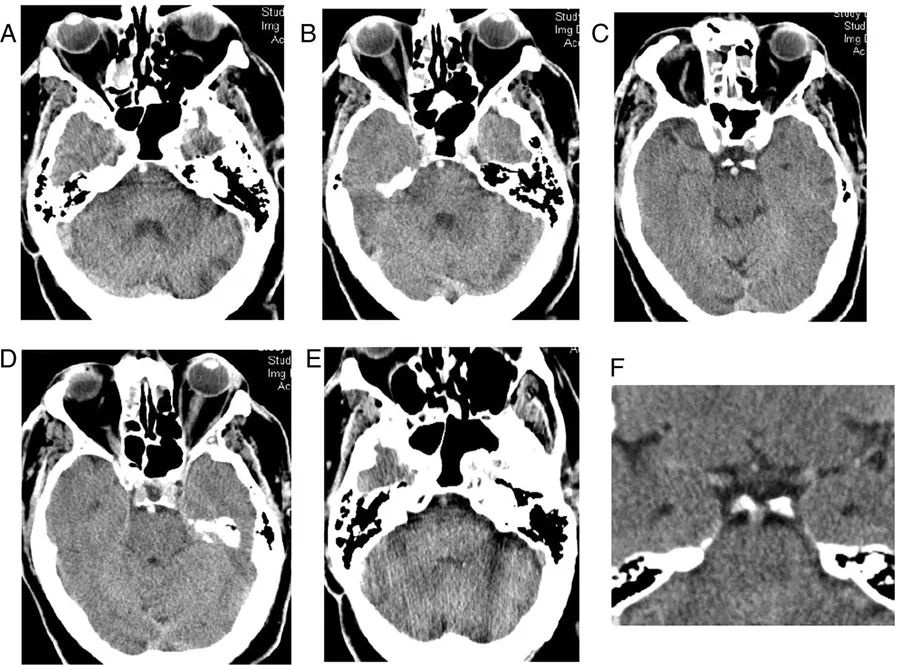

例1

图1  60岁男性,急性缺血性脑卒中,A~E:CT平扫;F:血管造影冠状位重建

左侧颈内动脉末端、大脑中动脉及其大脑外侧裂的分支可见高密度血栓影。大脑中动脉高密度征的特异性几乎为100%,但敏感性只有5%~50%。

此外,左侧大脑外侧裂周围皮质可见界限不明确的稍低密度影,豆状核模糊,反映了早期缺血性改变。CT血管造影证实左侧颈内动脉末端、大脑中动脉的M1段和M2段闭塞,远端可见少量侧支循环血流。